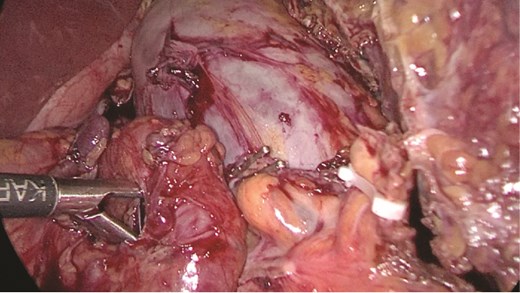

Multidisciplinary discussion was held to evaluate the most appropriate course of action for the patent condition, and the consensus was reached to pursue embolization as a first intervention. Embolization was performed by interventional radiology with no complications post-procedure, and the patient was optimized prior to her procedure. Patient was taken to the operating room in stable conditions. The spleen was enlarged around 20 cm. Inferiorly, the omentum and part of the transverse colon was attached to the spleen (Fig. 3), so we freed the omentum from the splenic tissue. The dissection continued until reaching short gastric vessels and entering the lesser sac (Fig. 4). Once the lesser sac was entered, the splenic vessels were identified (Figs 5 and 6), the splenic vein was hugely dilated with multiple collateral branching vessels at the hilum. Gaining posterior mobilization of the vein was challenging. The splenic artery was tortuous from the insertion around itself (Fig. 7). After complete mobilization of the fundus, we elected to divide each vessel starting with the splenic artery so we can achieve full mobilization of the vein (Fig. 9). After controlling the splenic artery, the splenic vein was dissected proximal to the splenic hilum (Fig. 8). It was hugely dilated and its wall is thickened secondary to AV fistula. It was difficult to achieve circumferential dissection, so we decided at that moment to convert to laparotomy to complete ligating the vein and to retrieve the specimen (Fig. 10a and b).

Splenic vein mobilized from the side. Clips seen on branches of the vein.